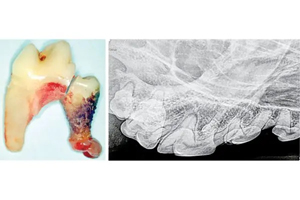

Have you heard of the chevron lucency?

Interpreting dental radiographs in dogs and cats can be challenging, particularly when assessing teeth for possible endodontic disease. This column discusses the classic radiographic signs individually.